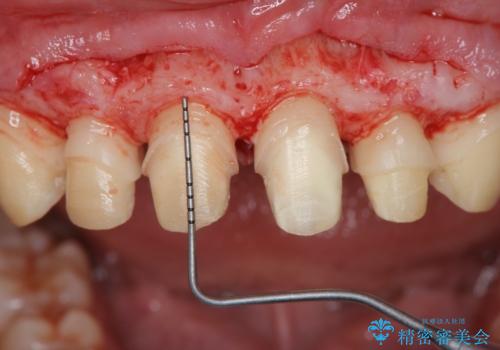

ただ、白いオールセラミッククラウンを製作・装着するのではなく、将来にわたり安定した状況を獲得するため、歯周外科を行い歯ぐきと周囲の歯槽骨の形態を整えていきます。

歯周外科を行ったことで、歯ぐきの形態や腫れが改善され、審美性だけでなく清掃性も大きく改善することができました。